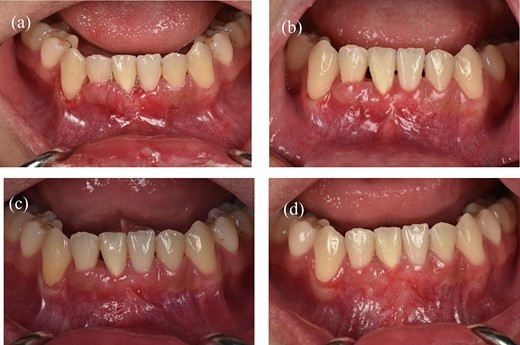

Clinical images of postoperative follow-up. (a) 3 weeks. (b) 2 months. (c) 6 months. (d) 12 months.